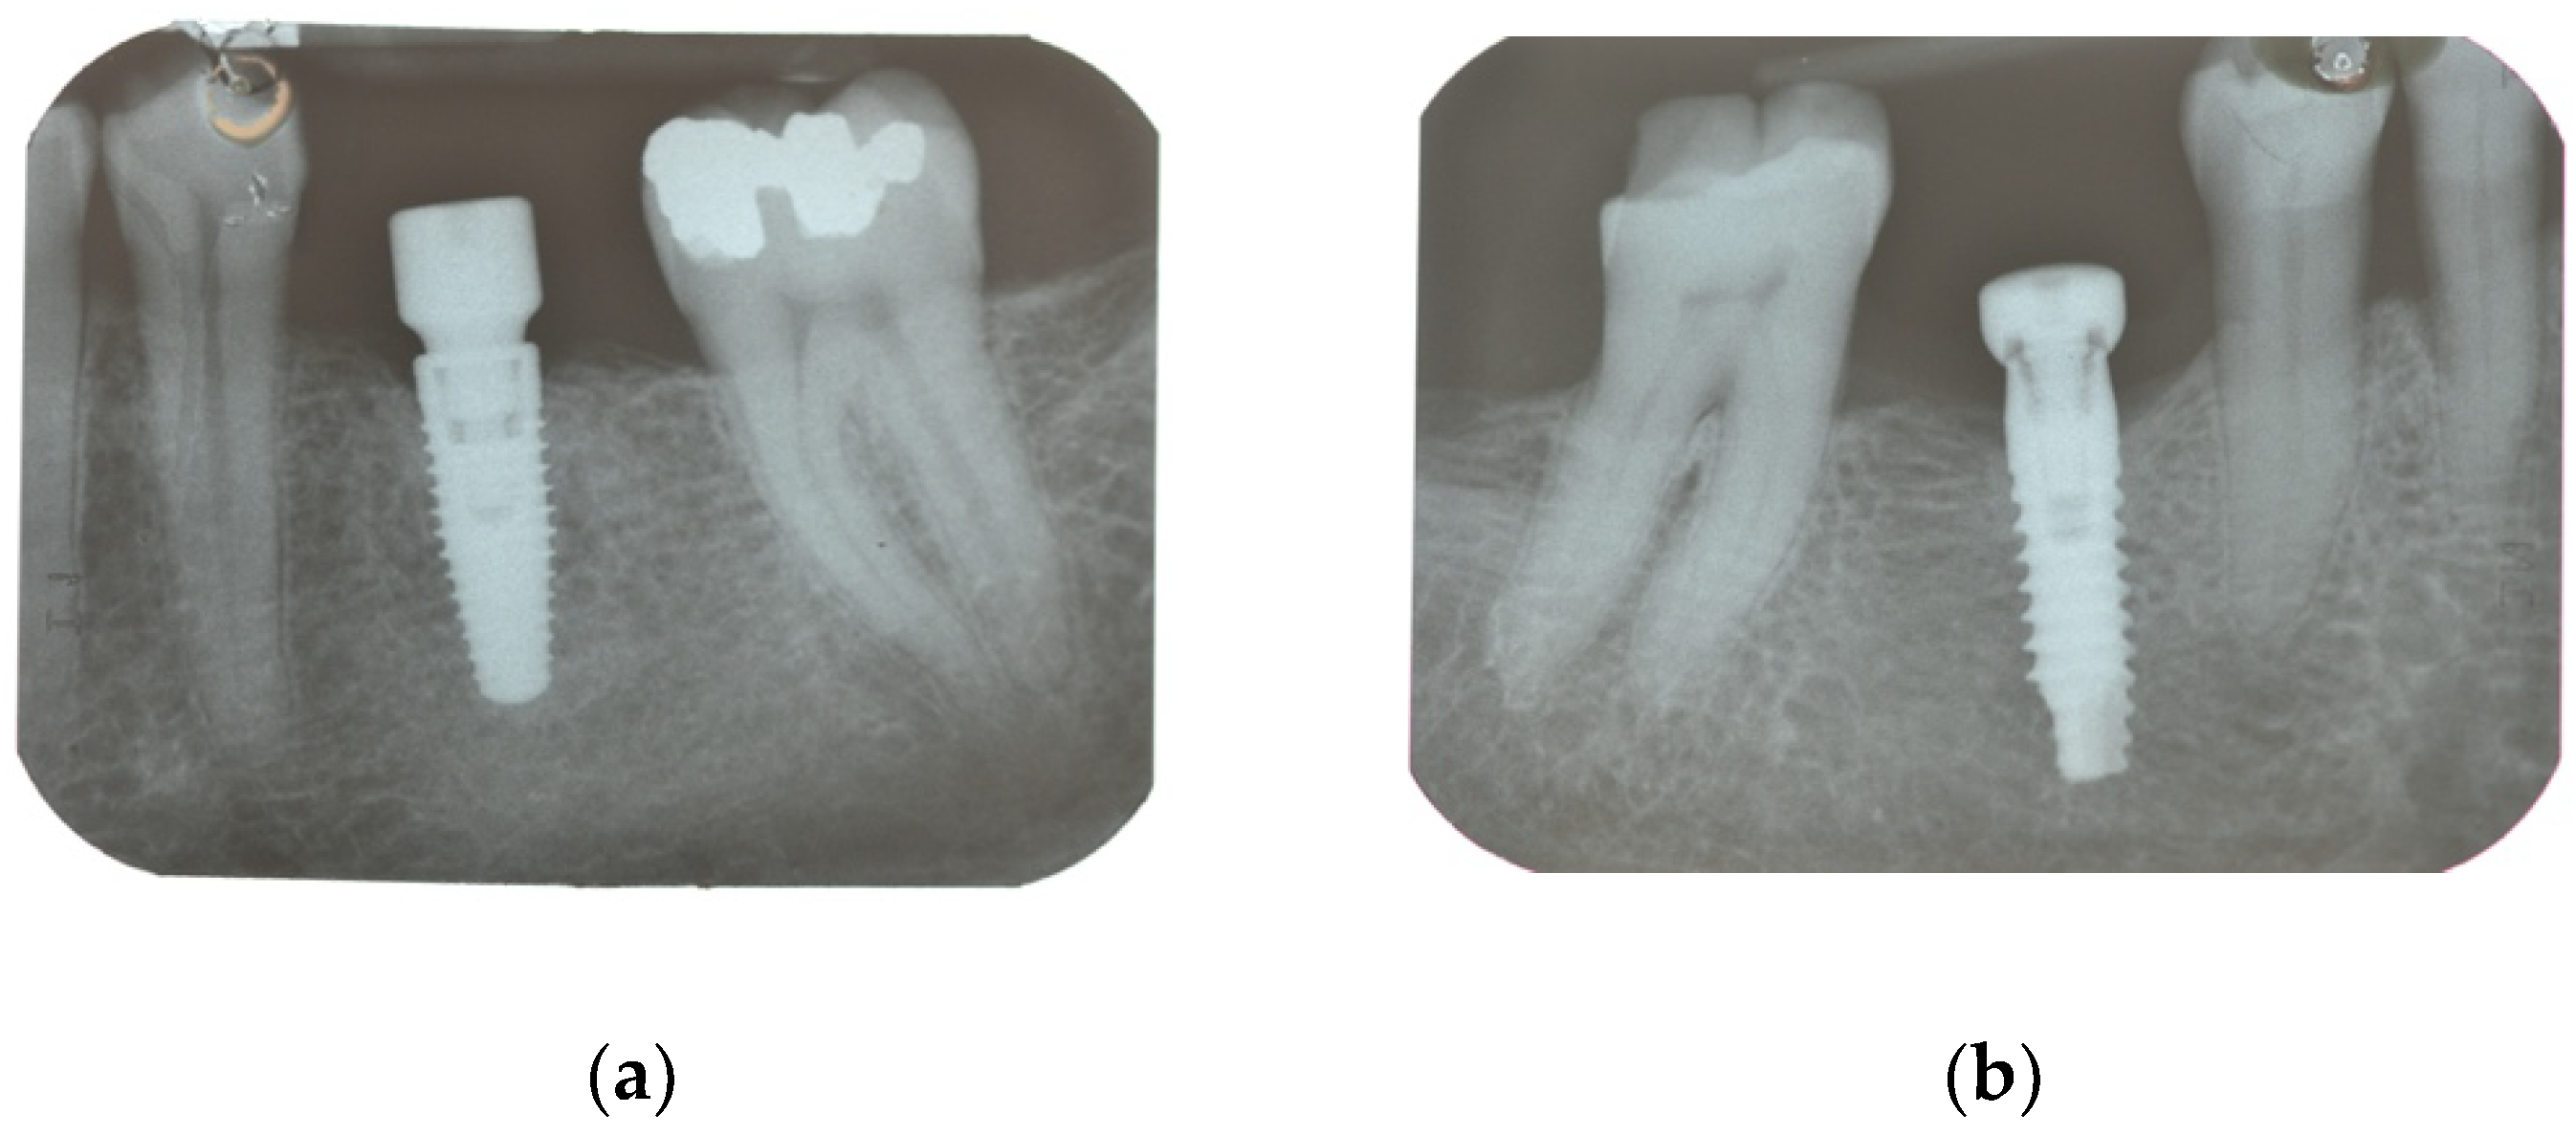

| Secondary Outcome | Marginal bone loss (MBL) | Marginal bone level changes were assessed using intraoral digital periapical radiographs at implant placement (baseline), and at after one year on function. Intraoral radiographs were taken with the parallel technique with customized holder. All the radiographs were evaluated under routine conditions. The software has been calibrated for every single image using the known distance of the implant diameter or length. The distance from the reference point at the implant neck to the first bone to implant contact were taken as the horizontal marginal bone level at both mesial and distal aspects. The average radiographic values of mesial and distal measurements were taken for each implant. Variation of the marginal bone levels at different time was taken as marginal bone loss. |

| Implant placement | 0.04 ± 0.06 (0.00 to 0.07); n = 15 | 0.01 ± 0.02 (0.00 to 0.02); n = 15 | 0.128 |

| One-year follow-up | 0.99 ± 0.71 (0.61 to 1.36); n = 14 | 0.65 ± 0.48 (0.40 to 0.91); n = 13 | 0.166 |

| Difference | 0.96 ± 0.72 (0.58 to 1.34) | 0.65 ± 0.48 (0.40 to 0.90) | 0.192 |